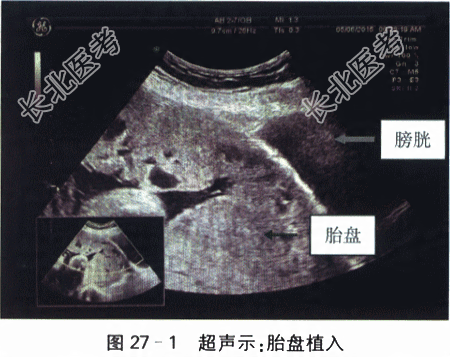

孕妇,34岁,因“G₄P₁,孕34⁺⁴周,凶险性前置胎盘,胎盘植入可能”入院待产。平素月经规则18,5/28天,量中,无痛经,LMP2022-6-20,EDC2023-3-27,停经30⁺天,查尿β-HCG(+),孕2月时出现轻微早孕反应(恶心、呕吐),孕5月出现胎动,胎动好,定期在外院做产前检查,无创DNA检查示低风险,早孕期B超检查提示胎盘边缘完全覆盖宫颈内口,植入不能排除;患者定期复查B超检查均提示前置胎盘,胎盘植入可能,孕期无阴道出血,孕32周MRI检查提示“植入性胎盘可能”;OGTT:4.46-10.35-8.79mmol/L,无多饮多尿多食,饮食控制后自测血糖均正常范围,产检尿酮(-);超声示胎儿发育与孕周相符。无外伤手术史,无高血压、心脏病、糖尿病等慢性疾病史。生育史1-0-3-1,2013年因羊水过少行剖宫产术,2014年末次人流。体格检查:神清,营养中等,无贫血貌,水肿(-),T37.0℃,P80次/min,R20次/min,BP110mmHg/70mmHg;心律齐,有力,各瓣膜听诊区未闻及杂音;双肺呼吸音清,未闻及干湿啰音;肝脾未触及,腹膨隆,神经系统(-)。产科检查:胎位LOA,胎动好;腹围95cm,宫高34cm胎儿体重估计2600g。骨盆测量:23-26-18-8.5(cm)。实验室和影像学检查:血Rt:WBC10.60×10⁹/L,N78.7%,Hb100g/L,PLT277.00×10⁹/L,肝肾功能指标、DIC、EKG等均正常。B超检查:胎盘位于子宫下段、完全覆盖宫颈内口,子宫下段前壁肌层尚可见,厚约6mm,与胎盘之间分界欠清,近宫颈内口处下段肌层局部血流丰富,似漩涡状(见图27-1)。MRI:完全性前置胎盘,伴胎盘植入。胎儿MRI未见明显异常(见图27-2)。